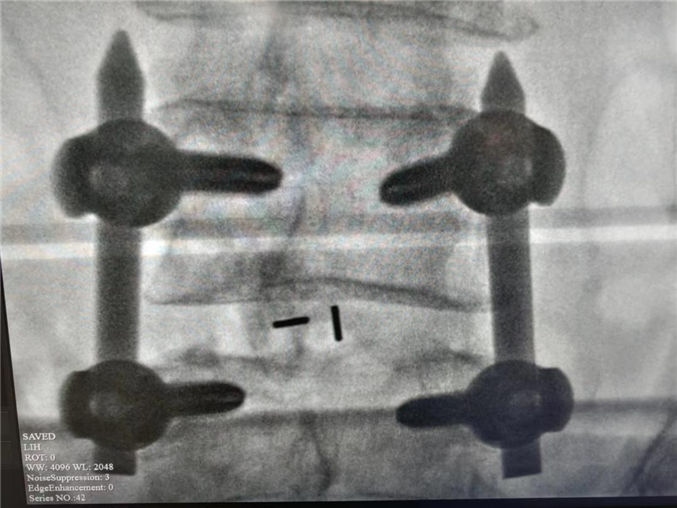

62岁的患者张先生,近2年来时常腰疼伴有左下肢疼痛,行放射线检查结果提示:腰4、5间盘突出,压迫硬膜囊,同时伴有脊柱不稳,行保守治疗效果不佳。患者就诊多家医院,最终选择我院骨科二病房住院治疗。经过和患者详细沟通及科室多次会诊后,骨科二病房团队最终为患者制定了腰4、5经皮椎弓根钉内固定、间盘镜下间盘摘除、椎间植骨融合内固定术的手术方案。术后患者腰疼及下肢的疼痛明显缓解,现已康复出院。

大多数腰椎间盘突出症患者选择保守治疗,但当保守治疗无效并影响生活质量时便可以考虑手术治疗。传统的腰椎间盘突出症需要行开放手术也就是传统的大切口,广泛剥离腰旁组织来完成,手术创伤大,手术效果不确切。近几年来我科已经自主完成了多例经皮椎弓根钉内固定术、间盘镜下单纯髓核摘除术,在此基础上,我们又进一步将两种微创手术相互融合、相互叠加,开展类似于MIS-TILF的术式即经皮椎弓根钉+间盘镜下间盘摘除植骨融合内固定术。该术以其微创切口,不用广泛剥离椎旁肌,创伤小恢复快等优势为广大腰间盘突出症患者带来了新的治疗选择。